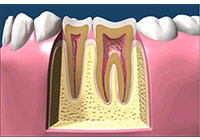

齲齒由口腔中多種因素復合作用所導致的牙齒硬組織進行性病損,表現為無機質脫礦和有機質分解,隨病程發展而從色澤改變到形成實質性病損的演變過程。齲齒是細菌性疾病,因此它可以繼發牙髓炎和根尖周炎,甚至能引起牙槽骨和頜骨炎癥。(圖01~04)

圖1

圖2